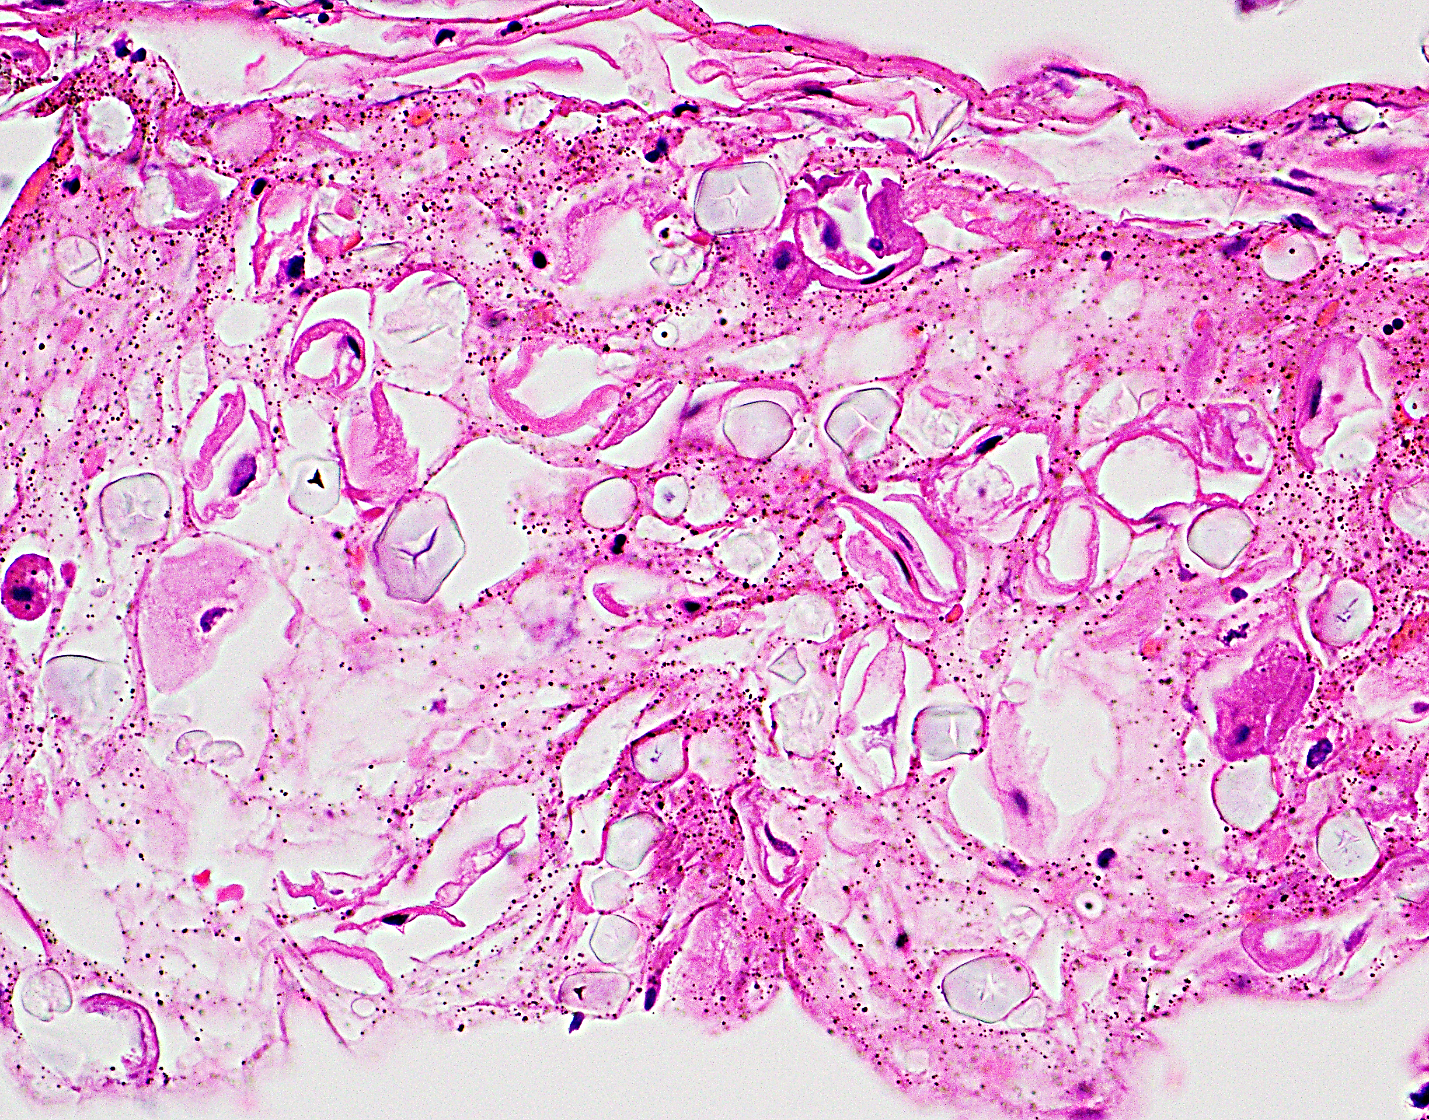

38 year old woman with esophagus ulcer; Abstract eosinophilic esophagitis (eoe) is a new disease. Multinucleated giant cells, ballooning degeneration infectious esophagitis. Cytomegalovirus esophagitis is a form of esophagitis associated with cytomegalovirus. Histology for hsv esophagitis shows nuclear molding, margination, and multinucleation of infected. „ histology shows koilocytosis (atypical ringed nucleus), giant cells. Herpes esophagitis is one of the infectious esophagitis that usually affects immunocompromised patients. Labetoulle m, maillet s, efstathiou s, dezelee s, frau e, lafay f. Looking to download safe free latest software now. The cases of esophagitis caused by hsv can be endoscopically characterized by multiple ulcers as they are punched out with sharp edges or borders. Diagnostics and treatment of infectious esophagitis: Clinical guidelines of the russian gastroenterological association. Esophagitis, also spelled oesophagitis, is a disease characterized by inflammation of the esophagus.

Herpes esophagitis is a viral infection of the esophagus caused by herpes simplex virus (hsv). „ histology shows koilocytosis (atypical ringed nucleus), giant cells. Florid herpes esophagitis with diagnostic cowdry a inclusions and multinucleated cells with nuclear. Diagnostics and treatment of infectious esophagitis: Abstract eosinophilic esophagitis (eoe) is a new disease. Candidal esophagitis, mimicking cardiac achalasia. Labetoulle m, maillet s, efstathiou s, dezelee s, frau e, lafay f. Acute esophagitis occasionally afflicits the esophagus.

Although no single feature defines eoe. Cmv esophagitis has been reported in patients who have undergone. The cases of esophagitis caused by hsv can be endoscopically characterized by multiple ulcers as they are punched out with sharp edges or borders. Cobblestone esophagitis (эзофагит со слизистой булыжной мостовой). Assessment of their localization and connections to the. This condition occurs in the setting of patients with a weakened immune system who are susceptible. Multinucleated giant cells, ballooning degeneration infectious esophagitis. Esophagitis may cause odynophagia and even esophageal hemorrhage, which is usually occult but can be massive. Cytomegalovirus esophagitis is a form of esophagitis associated with cytomegalovirus. Histology for hsv esophagitis shows nuclear molding, margination, and multinucleation of infected. Also, they may be deep to the surface. Labetoulle m, maillet s, efstathiou s, dezelee s, frau e, lafay f. For the purpose of histological descriptions, the esophagus is subdivided into upper (entirely skeletal muscle in the muscularis externa),middle (mixed smooth and skeletal muscle) and lower (entirely.